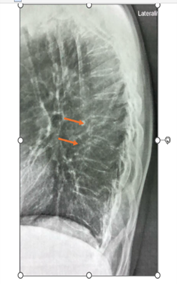

A interpretação padronizada das radiografias é essencial para evitar o subdiagnóstico. Termos como acunhamento, que descrevem uma redução na altura anterior do corpo vertebral, podem indicar a presença de fratura e devem ser claramente reportados como tal no laudo.8 O método semiquantitativo de Genant é a ferramenta recomendada para classificar a gravidade das fraturas vertebrais (graus 1 — leve, 2 — moderada e 3 — grave), fornecendo uma linguagem universal que auxilia na avaliação clínica.8

A identificação de uma fratura vertebral ou de múltiplas fraturas vertebrais em uma radiografia muda radicalmente o estadiamento da paciente.2,4,7 De acordo com as diretrizes da American Association of Clinical Endocrinologists (AACE)7 e o consenso da Sociedade Brasileira de Endocrinologia e Metabologia (SBEM/ABRASSO), esses achados classificam a paciente na categoria de risco muito alto de fratura, independentemente do seu T-score na densitometria.4 Essa reclassificação é um passo fundamental para individualizar e intensificar o tratamento.4